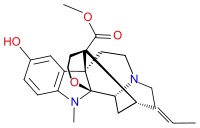

Opium alkaloids and derivatives

Phenanthrenes naturally occurring in (opium):

Preparations of mixed opium alkaloids, including papaveretum, are still occasionally used.